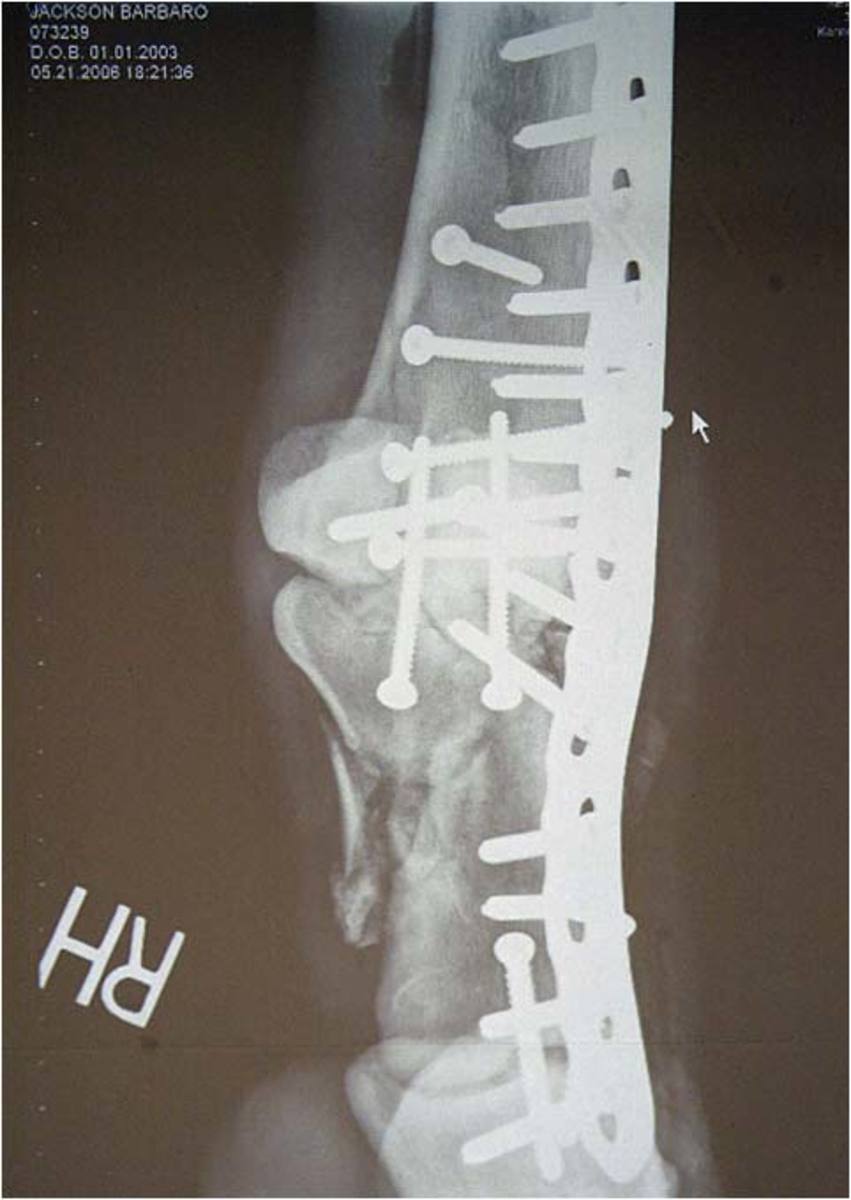

It took more than five hours of surgery and multiple screws to repair three broken bones in Barbaro's right rear leg.